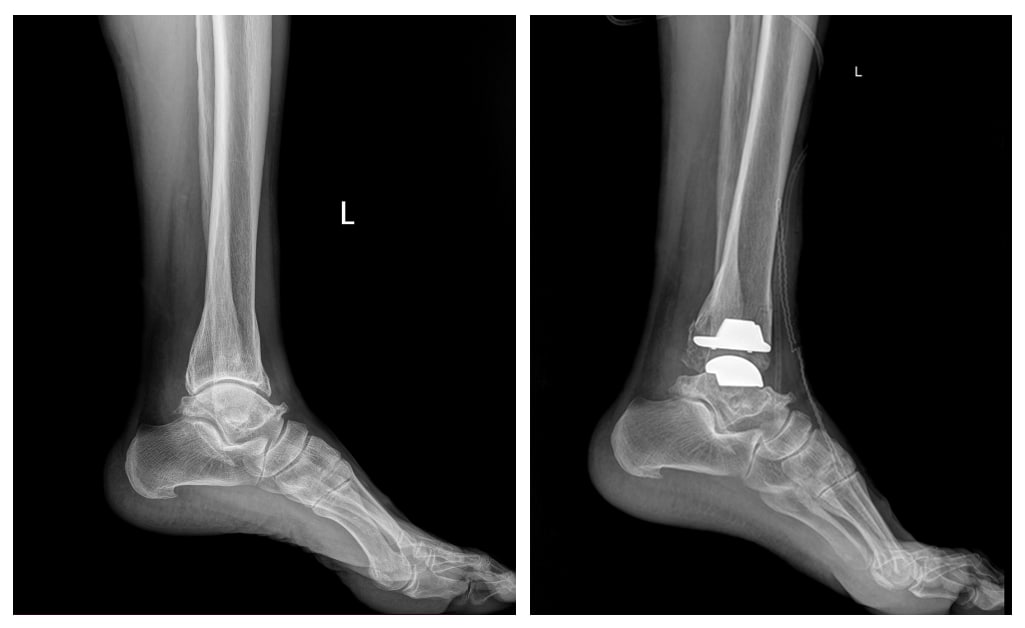

Гэмтэл Согог Судлалын Үндэсний төвийн Насанд хүрэгсдийн гэмтэл согогийн тасгийн их эмч Г.Бадамгарав, Ш.Баасансүрэн, Ц.Батбаяр нараар ахлуулсан мэс заслын баг БНСУ-ын Йонсей Гунвоо эмнэлгийн захирал Eui Hyun Park болон эмч мэргэжилтнүүдтэй хамтран Монгол Улсад анх удаа шагайн үений хүнд хэлбэрийн артроз өөрчлөлтийн үед хиймэл үе суулгах мэс засал, эмчилгээг амжилттай нэвтрүүллээ.

Энэхүү орчин үеийн дэвшилтэт мэс засал эмчилгээг өөрийн оронд нутагшуулснаар шагайн үений артрозоор өвчилсөн олон иргэдэд өвдөлт зовууриасаа салах, амьдралын чанарыг сайжруулах боломжийг олгож байгаа юм.